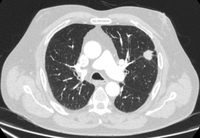

PET CT scan with 18-fluorodeoxyglucose (18-FDG) showing a low uptake in a semi-solid right upper lobe posterior lesion. Surgical resection confirmed adenocarcinoma with primarily lepidic pattern

From the collection of Dr George Tsaknis, MD, PhD, FRCP(London), MRQA, MAcadMEd, PGCert; used with permission